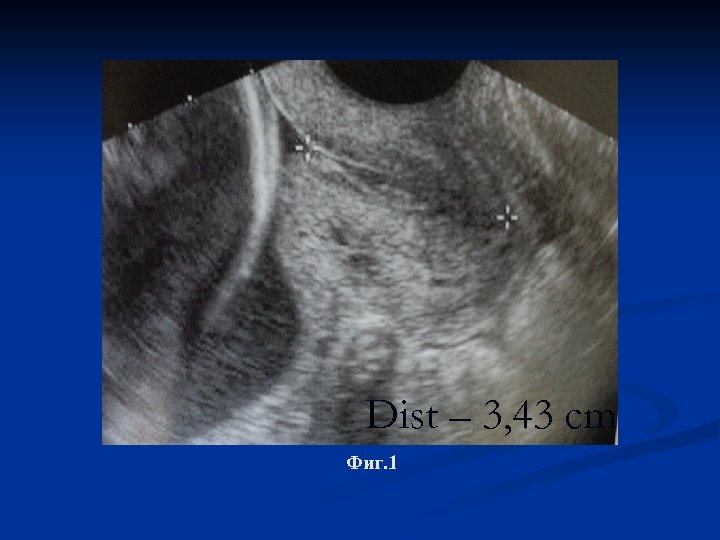

Фиг. 3